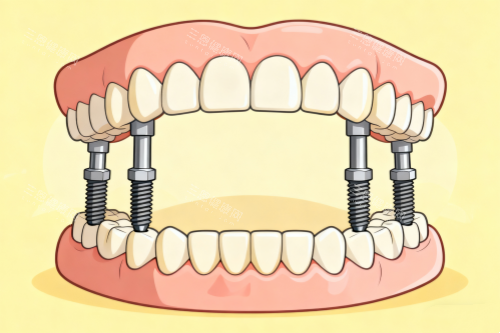

All-on-4即刻负重技术:针对半口或全口缺牙患者,需要植入4颗种植体即可修复完整牙列,手术当天即可戴牙进食,相比传统种植周期缩短3-6个月。

对于半口或全口缺牙患者,医院提供All-on-4半口种植方案,价格4.8万元起,相比传统半口种植费用降低约40%。所有种植价格包含术前检查、手术费用、种植体和修复冠费用,以及术后定期复查服务。医院支持多期付款,并与多家银行合作提供免息多期服务,减轻患者经济压力。